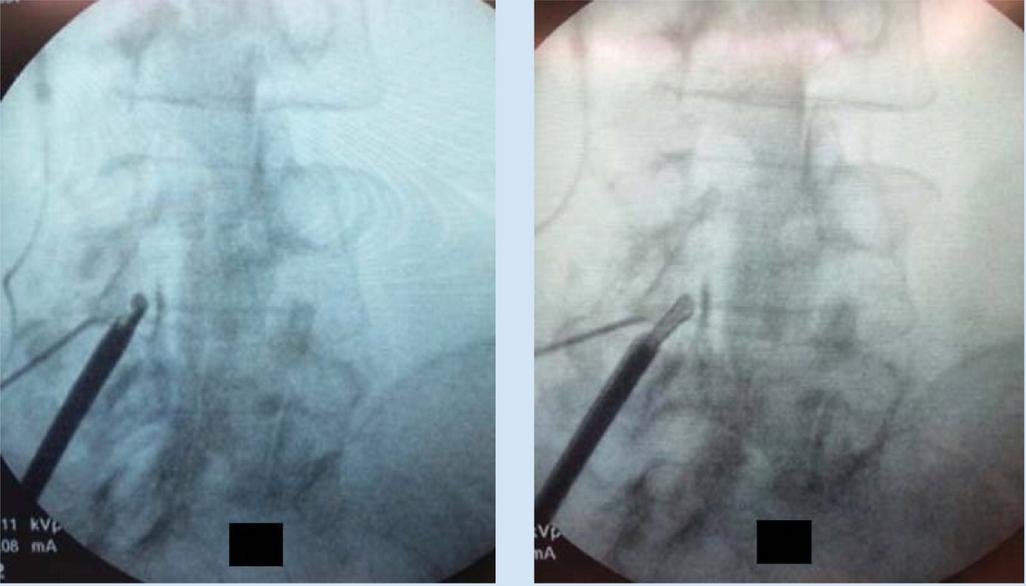

1. OperativeLevelIdentification:Identifytheoperative levelusingfluoroscopy.

PatientPositioning:Prone(thoracolumbar)forneedle placementfromeithersideandeasierpositioningofCarm Cushionstosupportheadandbody Adedicated biplanefluoroscopysuiteispreferred,butatleastone C-armunitisnecessary

Needleplacement:

Transpedicular:needlethroughfulllengthofpedicle a

Parapedicular:needlealongthelateralcortexof pedicle b

APviewsafetyconsiderations;(a)keeptomedialborderof pedicleinordertoavoidspinalcord/thecalsac,(b)don’t strayawayfromwithinpedicularborders,thiswillensure safetyofnervesandnerveroots lateralviewsafetyconsiderations;(a)cannulatipshouldbe seenattheposteriorbodywallinthelateralview,(b)the aorta/inferiorvenacavacanbedamagediftheanterior vertebralbodyispenetrated,(c)penetratingtheinferior pediclewallasaresultofimpropertrajectorycancause nervedamage

5. Cementplacement:fluoroscopicmonitoringis importanttoensurecementremainswithintheareaof target Lateralviewsaremoreimportantasitenables theevaluationoftheposteriorpositionofcement relativetospinalcanalandneuralforamina

6. ProcedureCompletion:postprocedureradiographsare takenandpatientismonitoredfor1-2hoursafter, includingneurologicassessment

Figure13:Illustrationsof vertebroplasty.

A)Preoperativeplanningofentry pointsandtrajectory(yellow: bipedicularapproach;purple: unipedicularapproach;red:medial pedicularborder),

B)Simplifiedschematicsof relevantanatomicallandmarks andangulation

C)Approximatetrajectory, D)Lateralfluoroscopicviewof cementinjection